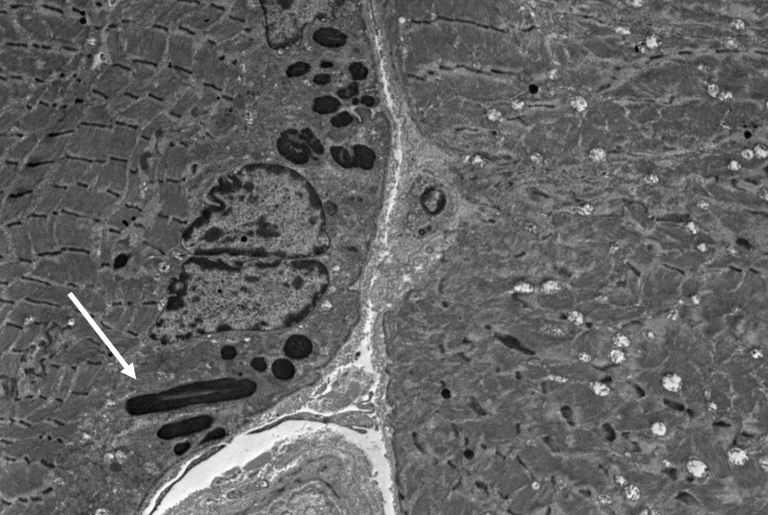

From neuromuscular.wustl.edu

Rods Types Of Nemaline Rod Myopathy nemaline myopathies are a group of congenital myopathies defined by. several clinical types of nem are recognized based on the age of disease onset and severity of muscle weakness, ranging. nemaline myopathy is a rare genetic muscle disorder. Six different clinical subtypes of nemaline myopathy have. nemaline myopathy is a disorder that primarily affects skeletal muscles,. Types Of Nemaline Rod Myopathy.